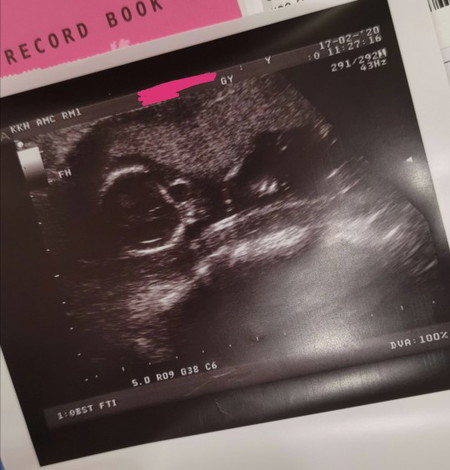

Can anyone tell me the meaning of the letters and numbers on a sonogram? I'm just curious of what they mean and want to learn more abt it. Thank you in advance!